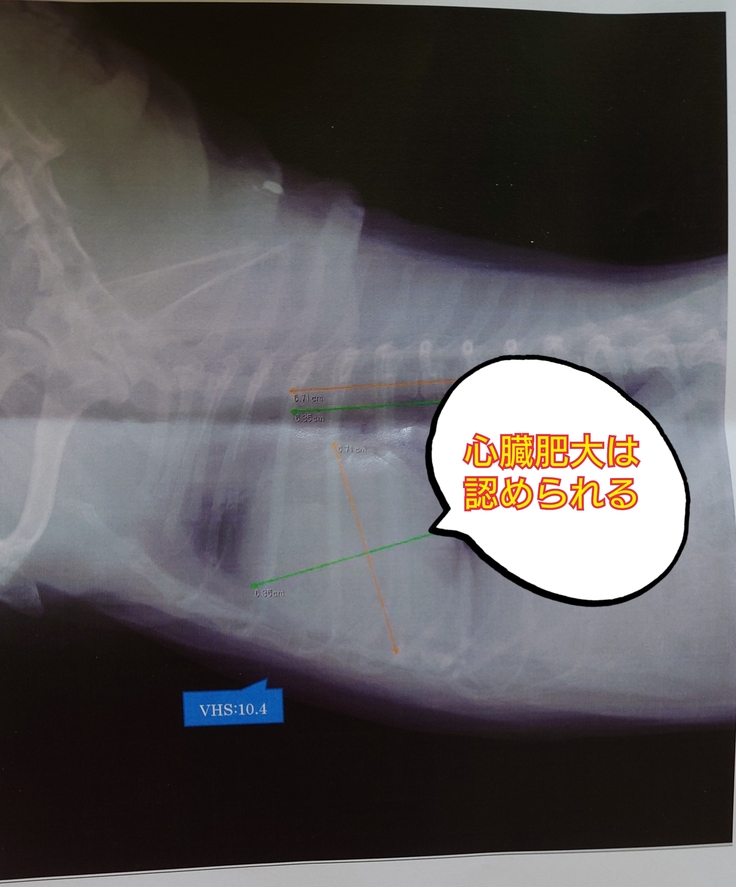

1.心臓、肺の状態について

やはり通常の子に比べて少し心臓が大きいのに変わりはないそうです。

幸運だったのは、2月に肺水腫を起こした時と大きさはさほど変わっていない、ということです。